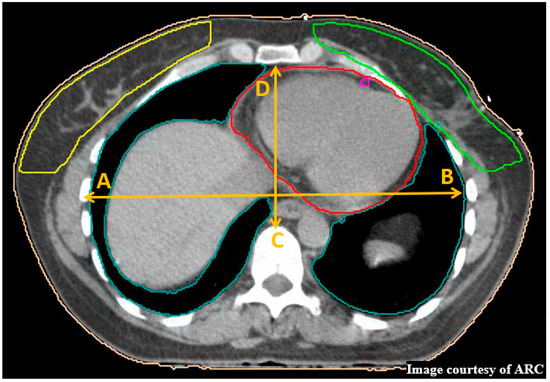

9. Maximum Heart Distance

10. Central Lung Distance and Chest Wall Separation

11. Statistical Analysis